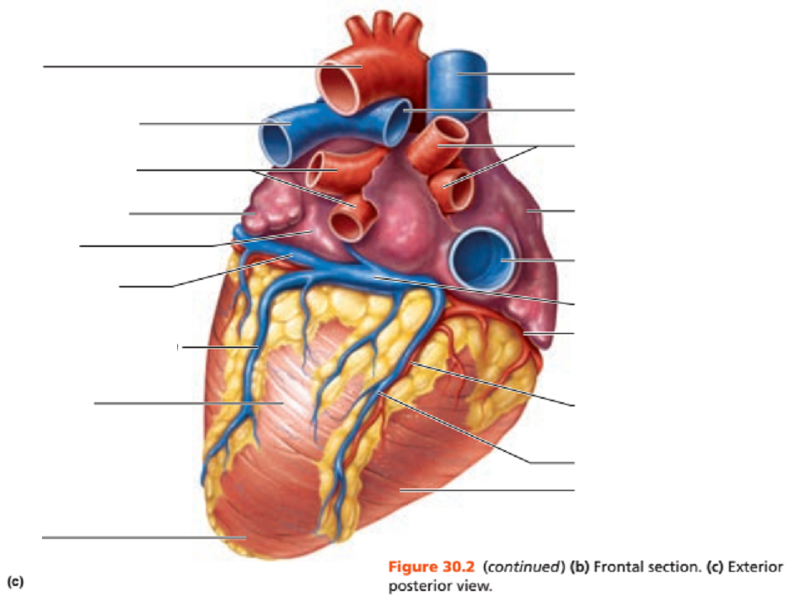

Name the missing parts.

Heart external posterior view

Name the missing parts.

External posterior view

Name the missing parts.

External posterior view